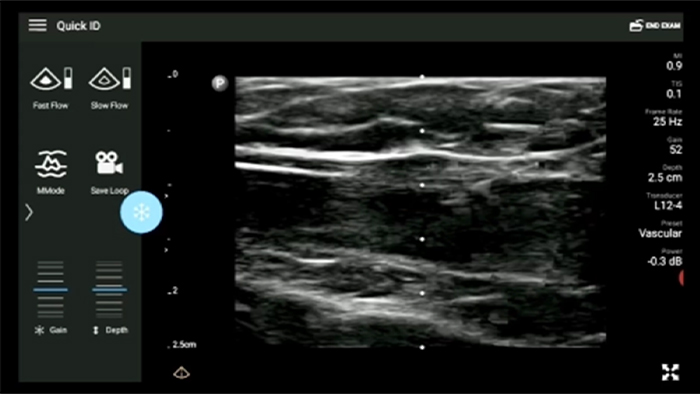

"… it frees both the patient and clinician from doing the procedure in the confines of the operating room or consultation room."Dr. Obispo Osteopath Musculoskeletal Specialist "… the unit fits into a small bag for easy transportation and is a very intuitive, easy to use ultrasound system."Dr. Sue Westerway Adjunct Associate

"… the unit fits into a small bag for easy transportation and is a very intuitive, easy to use ultrasound system."Dr. Sue Westerway Adjunct Associate

Lumify transducers for MSK

Lumify L12-4 broadband linear array transducer